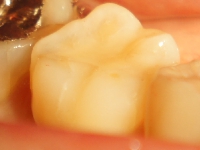

保険での虫歯治療(レジン修復)

➡

保険の虫歯治療でもここまできれいに回復できます。

ただ真っ白にするのではなく、歯本来のグラデーションを回復させています。

問題は保険の材料はあまり長持ちしないということです。